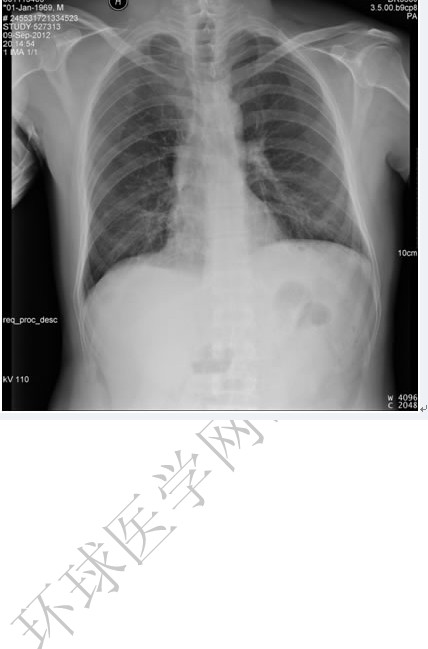

后肋骨折

圖示為右側3,5,6,7,8后肋骨折。

(1)后前位